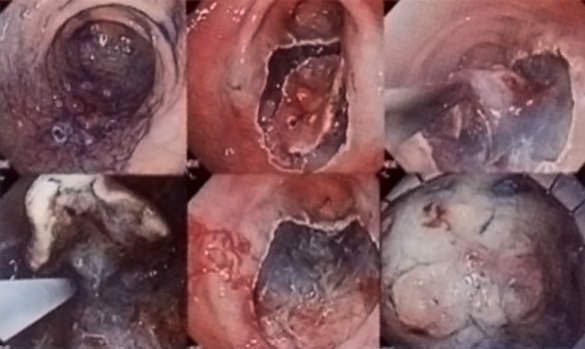

特に最新の高解像診断装置(狭帯域光観察、ハイビジョン拡大観察)により粘膜表面の微細構造や微細血管の観察から早期癌の内視鏡的治療前診断を行った上で、内視鏡的粘膜下層切開剥離術を用いた治療を積極的に行っております。切除後病理学的に治療効果を判定します。

ESD(内視鏡的粘膜下層剥離術)